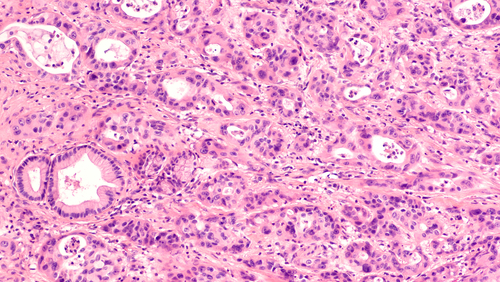

A phase I/II study sponsored by the National Cancer Institute lends support to further evaluating a potential new treatment strategy in advanced pancreatic adenocarcinoma (aPDAC)—more specifically, one that combines immune checkpoint inhibition and stereotactic body radiation therapy (SBRT).

Immune checkpoint inhibitors provide limited benefit in aPDAC, presumably because the tumour immune response has been stifled in the local tumour microenvironment. The investigators hypothesized that use of SBRT, which promotes antitumor immunity, either before or in tandem with PD-1/PD-L1 and CTLA-4 inhibitors, might provide the kick necessary to revive the immune system and enable the checkpoint inhibitors to successfully exert their therapeutic effects.